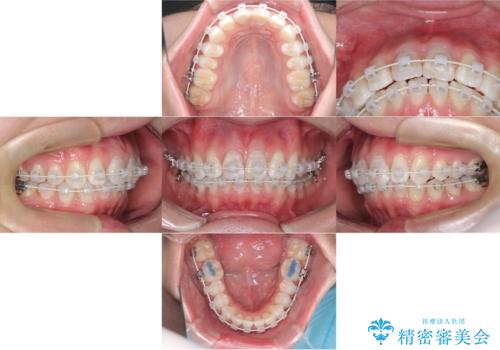

【ワイヤー矯正 11ヵ月で矯正終了!】歯のでこぼこを治したい!

- 矯正装置

- ワイヤー(審美装置)

- 11ヶ月

- 「歯のでこぼこを治したい 1年くらいで矯正を終わらせたい」を主訴に来院された患者様です。

叢生量は多く無く歯の傾斜も標準傾斜だったので歯は抜かずにワイヤー矯正で治療を行いました。

左側は2級傾向が強く臼歯の遠心移動をご提案しましたが、1年以内に矯正を終わらせたいという患者様のご意向で希望されず叢生を改善する矯正となりました。